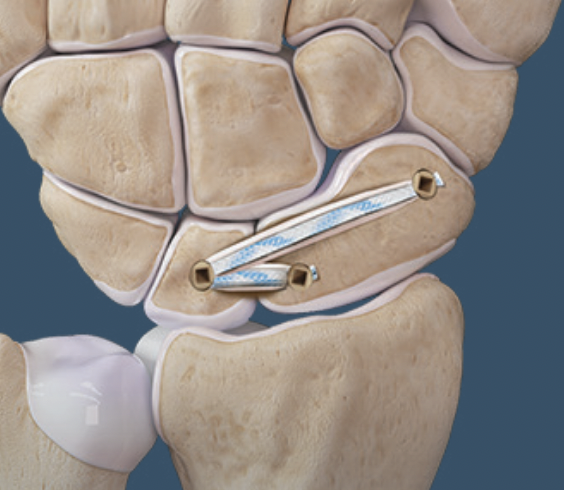

RASL (Reduction and Association ScaphoLunate)

Technique

Reduce SL joint with K wires

- secondary radial incision

- headless compression SL screw

- ? remove at 3 months

- creates mobile synchondrosis